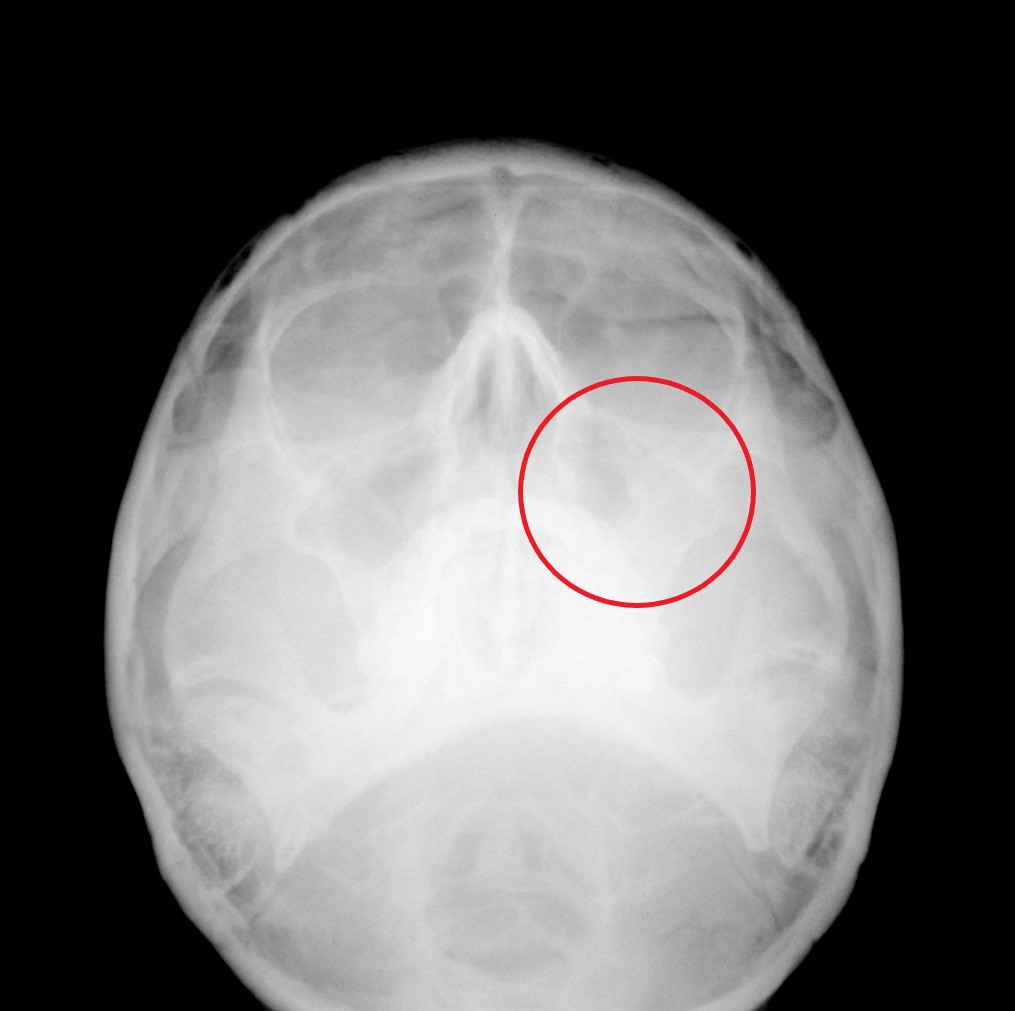

レントゲンをチェックすると↓

赤丸部分が白くなり、副鼻腔炎(ちくのう)の所見です。